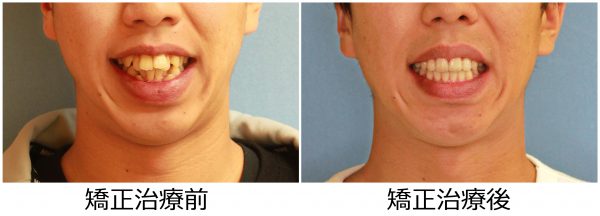

20歳 男性「 八重歯 出っ歯 を治したい」( 叢生、上顎前突症)

20歳の 男性です

「 ガチャガチャの歯ならびと ” 出っ歯” を治したい」との事で来院されました。

上下の歯が重なり合っています。

特に下の歯ならびの重なりは激しいです。

ガチャガチャが気になりますが、上の前歯が前に飛び出ているため、”出っ歯”の状態となっています。

横から診ると出っ歯の程度としても激しいですね。

重度の叢生を伴う 上顎前突症 です。

ガチャガチャの激しい歯ならびと

出っ歯のため口もとの雰囲気が良くありません。

(お顔の写真の使用にはご本人の承諾を頂いています)

人と会うときに ガチャガチャの歯ならびが社会人として恥ずかしく、

なんとか改善できないかと悩んでいたとの事でした。

治療を決断され(抜歯には抵抗があったそうです)

上下左右の抜歯を行い、ガチャガチャの歯ならびを整えました。

前歯もできる限り後方へ移動させ、口もとを下げました。

2018年の1月15日にスタートして 2019年の8月27日に 終 了 しました。

治療期間は 20か月 でした

激しいガチャガチャは改善され、八重歯の痕跡もありません。

良く動きました (#^.^#)

上の前歯もしっかりと下がり ”出っ歯” 感も解消されました。

治療前のレントゲン写真です。 下顎を中心として歯が著しく倒れこんでいます。

治療後のレントゲン写真です。倒れこんでいた歯がしっかりと排列されています。

口もとの 印象が 大きく変わり 人と接する時にも 自信を持てるとの事でした。

素敵な笑顔になりました! (#^.^#)

20歳 男性 著しい叢生を伴う上顎前突症 治療期間 20か月 唇側矯正装置(ホワイトワイヤー)と内側からの固定装置を使用した上下顎小臼歯抜歯治療 参考治療費 約67万円 (精密検査から終了まで) 矯正治療に伴う副作用の歯肉退縮、知覚過敏、歯根吸収などは認められませんでした。